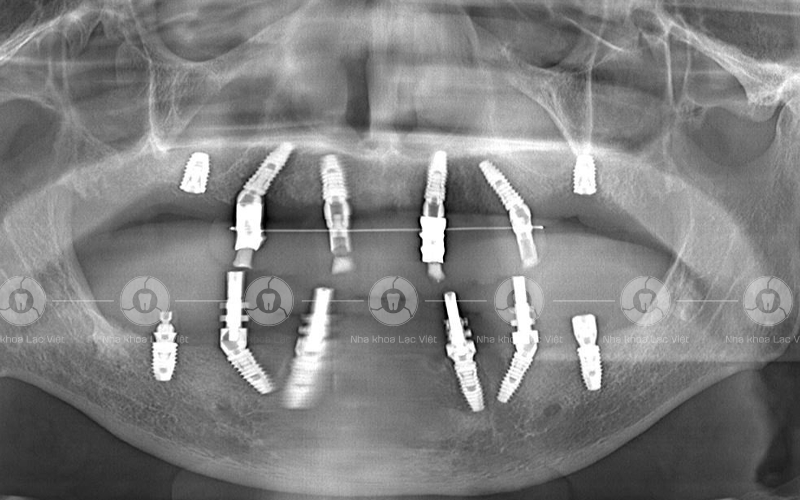

Hình ảnh phim chụp sau cấy ghép implant của chú Ánh (Ảnh: Nha khoa Lạc Việt)

Với tình trạng này đội ngũ bác sĩ tại nha khoa Lạc Việt đã quyết định đưa ra kế hoạch điều trị cho chú Ánh đó là khôi phục toàn diện hai hàm bằng phương pháp trồng implant kỹ thuật All-On-6 - Công nghệ độc quyền Safe-Tech.

Qua thăm khám, chụp phim CT Conebeam và dựa trên các dữ liệu ban đầu, bác sĩ tại Nha khoa Lạc Việt đánh giá chú Ánh gặp phải tình trạng cụ thể như sau:

• Mất toàn bộ răng hàm trên và nhiều răng hàm dưới

• Cầu răng sứ hỏng, viêm chân răng

• Mất thẩm mỹ khuôn mặt, chức năng ăn nhai kém